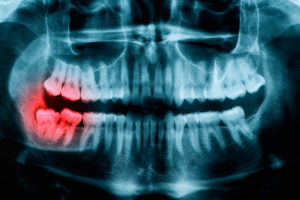

Осложнения прорезывания зуба мудрости

В этой статье мы расскажем про осложнения прорезывания зубов мудрости.

Удаление зубов мудрости (видео)

Удаление восьмых зубов

Если восьмерки в самом труднодоступном месте, то выход только один — это удаление.